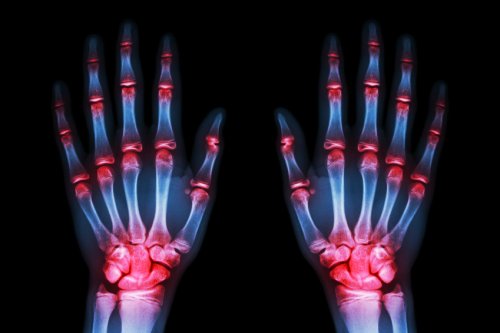

- Slitasjegikt er mest vanlig i hendene. (70 %)

- Som vi vet, når vi går til legen for hjelp, er det fordi vi ikke kan holde ut smertene lenger. Smertene i hendene er forferdelige, hendene blir numne om natten og får små deformiteter.